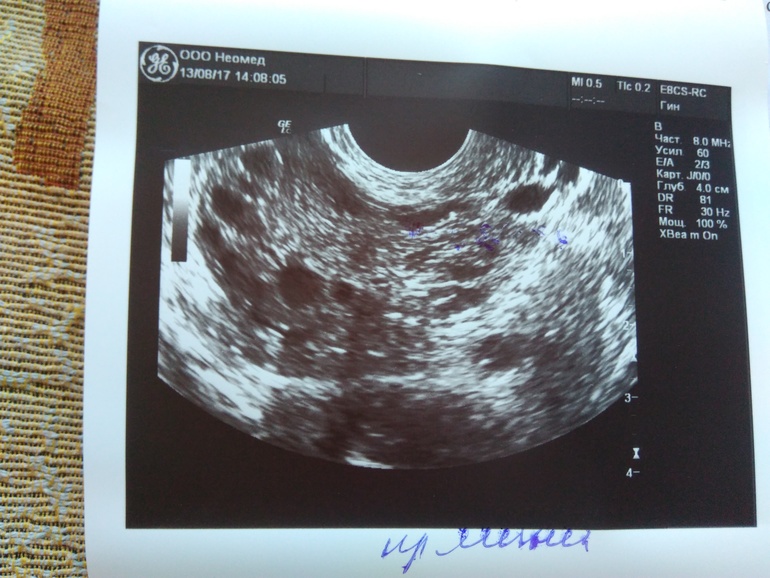

УЗИ на 13 дц

Узи Фолликулометрия